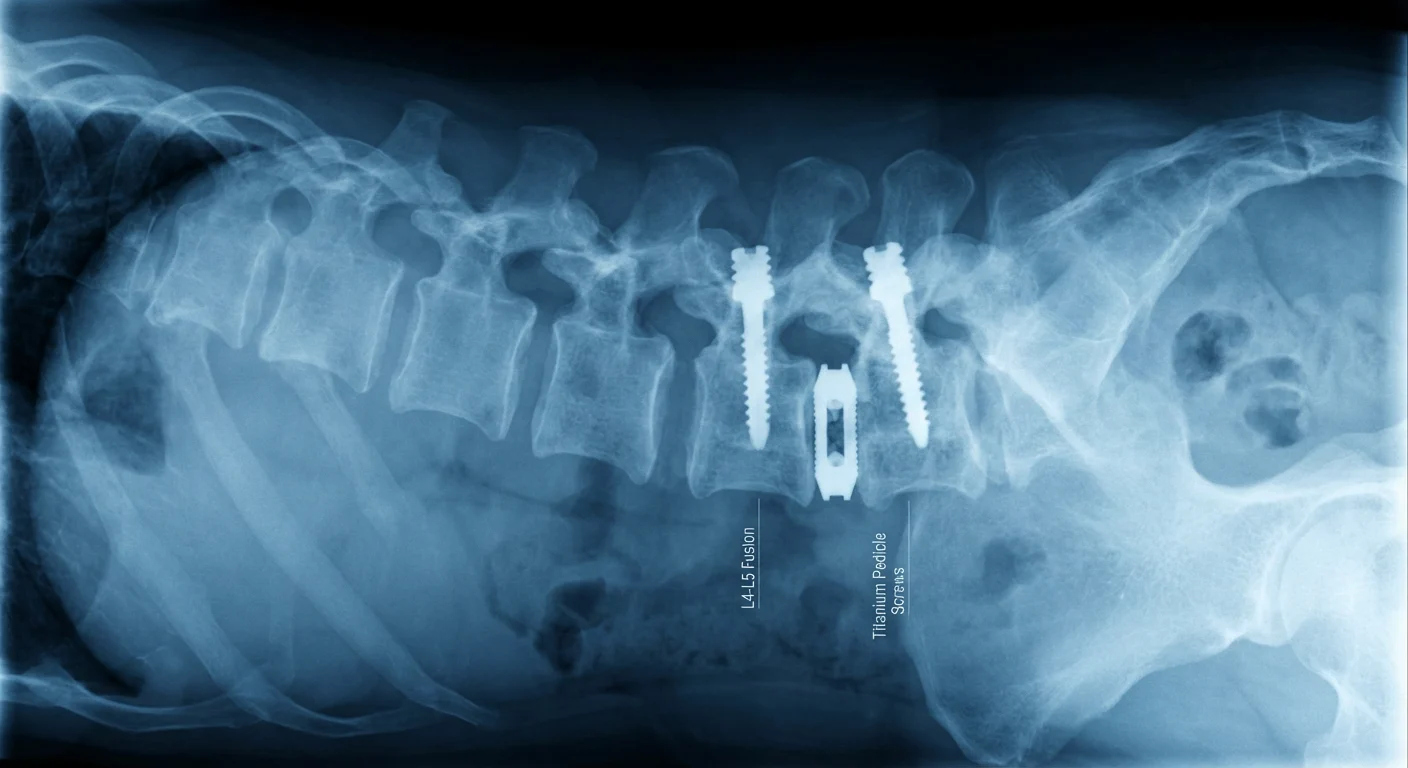

1. Orthopedic Implants: Restoring Movement

Titanium is the material of choice for hip and knee replacements, bone plates, and spinal fixation devices. Its primary advantage here is its exceptional strength-to-weight ratio. Titanium is as strong as steel but roughly 45% lighter. This is critical for patient comfort; a heavy implant could make a limb feel unnatural or sluggish, whereas titanium feels like a natural extension of the body.

The durability of titanium orthopedic implants is perhaps best illustrated by the comeback of golf legend Tiger Woods. After years of debilitating back pain, Woods underwent an Anterior Lumbar Interbody Fusion (ALIF) surgery. Surgeons placed a titanium cage and screws into his spine to stabilize the vertebrae. The titanium components were strong enough to withstand the immense torque and physical stress of a professional golf swing—forces that would destroy lesser materials. Thanks to the stability provided by these implants, Woods didn’t just recover; he returned to the pinnacle of his sport to win the 2019 Masters Tournament. His story serves as definitive proof that life with titanium implants doesn’t mean sitting on the sidelines.